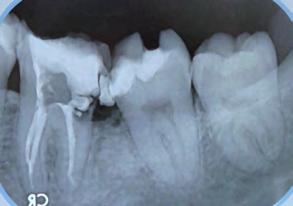

Paciente masculino de 29 años de edad, sin antecedentes médicos de interés acude al servicio de Cirugía Maxilofacial, el cual acude a la con sulta por odontalgía asociado al pri mer molar inferior izquierdo (Figura 1). Realizamos estudios radiográficos de dicho órgano (Figura 2), siendo valorado por especialista en prótesis y endodoncia quienes refieren no ser candidato para rehabilitación y tra tamiento de conductos con un pro nóstico poco favorable. Motivo por el cual se ofrece la opción de realizar TD del tercer molar inferior izquierdo al lecho quirúrgico del primer molar

Figura 2. Radiografía dentoalveolar inicial. Trasplante dental de terceros molares